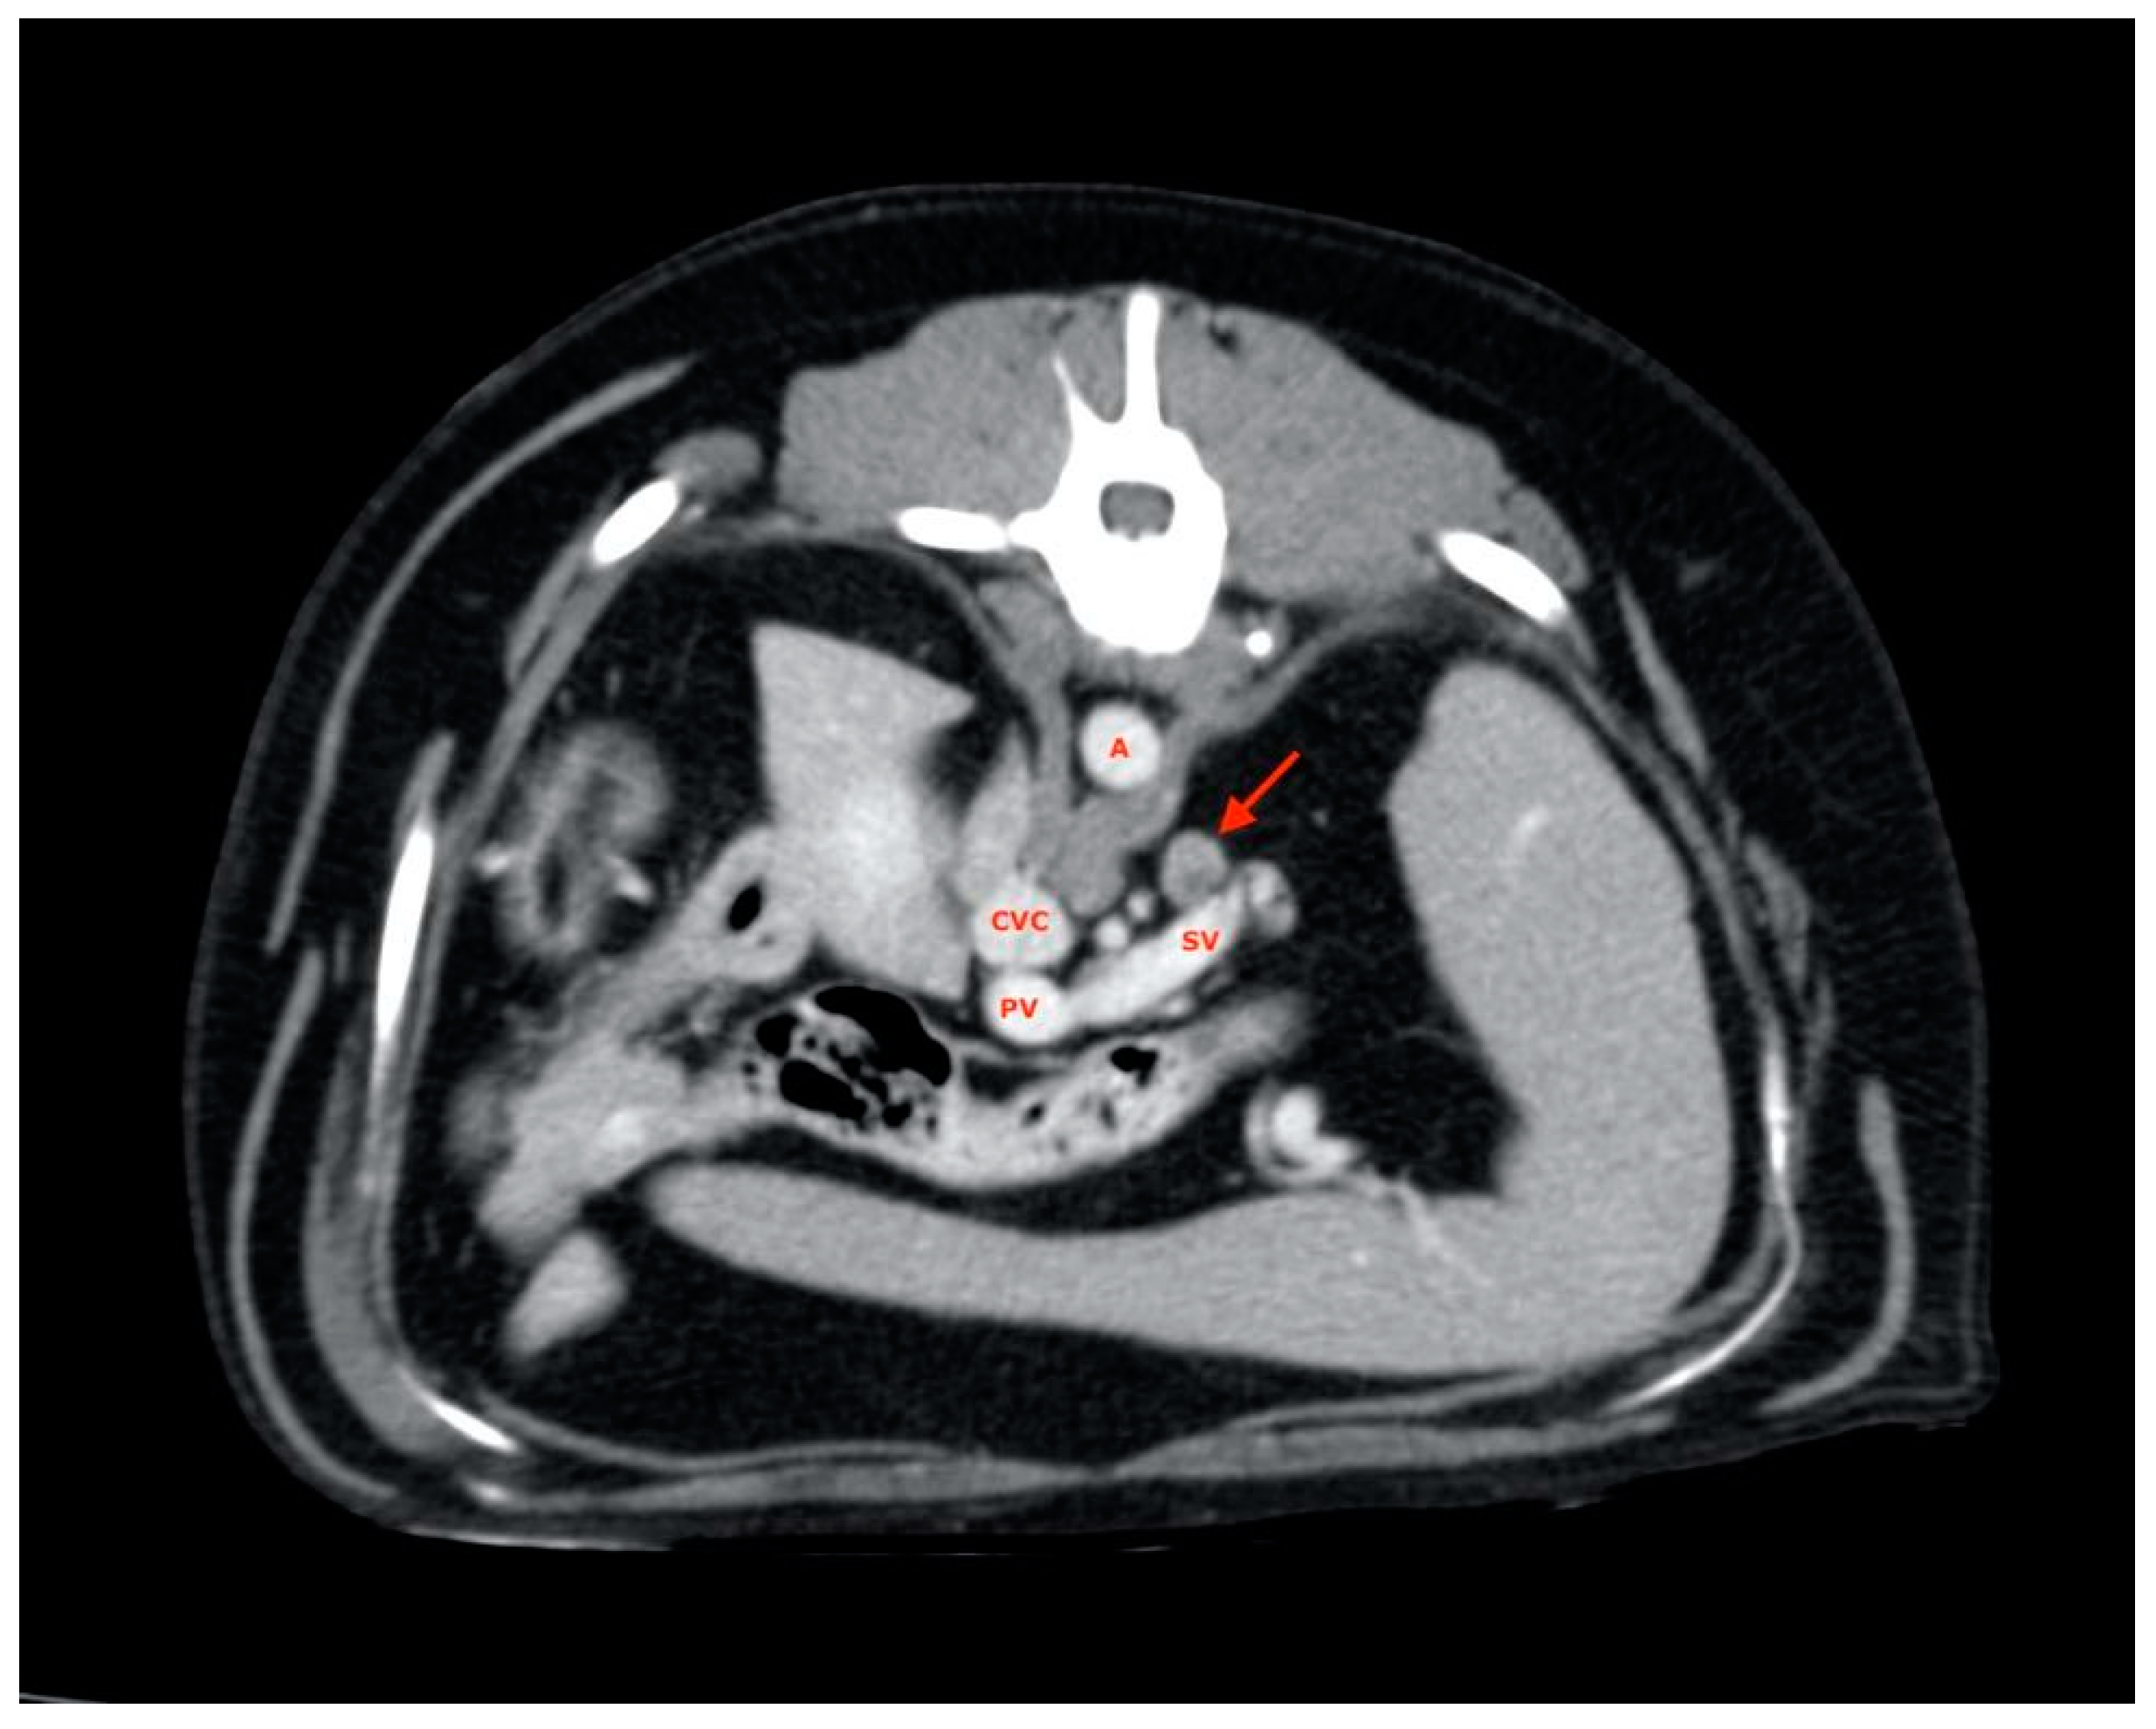

2.5. Measurements